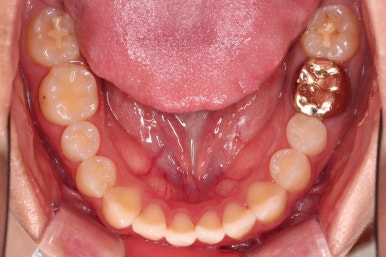

1. 처음 내원 시의 입안의 모습

부산치아교정잘하는곳 키다리아저씨치과에 처음 내원하셨을 당시의 입안 모습입니다.

얼핏 보면 많이 삐뚤어지지는 않은 편인데, 눈에 바로 띄는 앞니가 뻗쳐 있으면서 획 돌아있는데요. 정렬이 필요한 상황이었습니다.

어금니쪽은 많이 삐뚠 편은 아니었으며, 윗니 앞니가 많이 앞으로 뻗쳐 있는 상태였습니다.